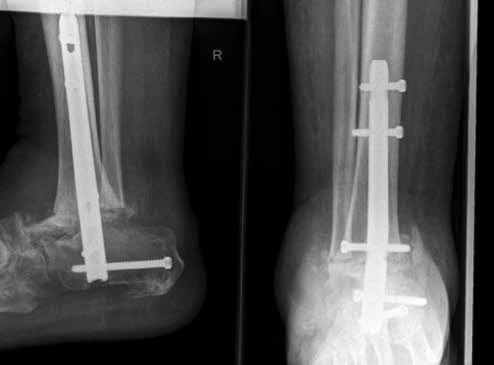

In ausgeprägten Fällen von Arthrose, oft mit Instabilität im oberen Sprunggelenk (Abb. 7), schwerwiegendem Funktionsverlust und starker Schmerzausprägung, ist nach wie vor die Arthrodese die Therapieoption der Wahl. Dadurch sollen die Achskongruenz wiederhergestellt und die Schmerzen eliminiert werden. Gleichzeitig bedeutet dieser Schritt jedoch, dass keine weitere operative Eskalation mehr möglich ist. Meist kommen die tibiotarsale oder tibiatalar-calcaneare Arthrodese zum Einsatz. Entscheidend für die Wahl des Arthrodeseverfahrens sind der Schweregrad der degenerativen Gelenkveränderungen, der Schmerz und die Stellungsverhältnisse im Subtalargelenk.

Eine Sonderform stellt die Talusnekrose dar, die ebenfalls zu schwerwiegenden Destruktionen und Achsfehlstellungen im OSG führt. Das Mittel der Wahl im fortgeschrittenen Stadium (Abb. 8a) ist hier die Arthrodese des OSG und des unteren Sprunggelenks (USG) mittels Arthrodesennagel (Abb. 8b).